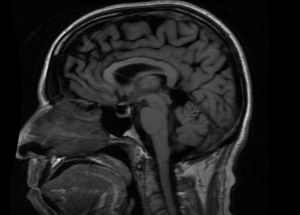

Diagnosis of ESS is most often with radiographic visualization of the findings through CT or MRI imaging of the brain and orbit with and without contrast [8](Figure 1). A normal midline pituitary stalk distinguishes the lesion from an arachnoid cyst.[9] With incidental findings in an asymptomatic patient (PESS), secondary causes need to be considered (SESS). Hormone testing may be considered for both symptomatic and asymptomatic patients due to the prevalence of hypopituitarism.[3] These include measuring cortisol, free thyroxine, estradiol or testosterone, insulin like growth factor 1 (IGF-1), and prolactin levels.[3]